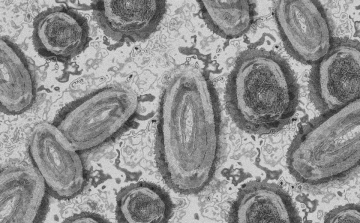

Meghaladta a 13 ezret a majomhimlő-fertőzöttek száma az Egyesült Államokban

Meghaladta a 13 ezret a majomhimlő-fertőzöttek száma az Egyesült Államokban, a legtöbb esetet Kaliforniában és New York államban regisztrálták.

Tovább nőtt a majomhimlő-fertőzöttek száma Magyarországon

Újabb kilenc, 23-50 éves férfinél igazolták a majomhimlő-fertőzést Magyarországon, ezzel 42-re nőtt a fertőzöttek száma - közölte a Nemzeti Népegészségügyi Központ (NNK) csütörtökön az MTI-vel.

Tovább nőtt a majomhimlő magyar fertőzöttjeinek száma

Újabb hat embernél diagnosztizálták a majomhimlő vírusát, így harmincra emelkedett az igazolt fertőzöttek száma Magyarországon - közölte a Nemzeti Népegészségügyi Központ (NNK) pénteken az MTI-vel.

Újabb hét magyarnál igazolták a majomhimlőt

Újabb hét embernél igazolták a majomhimlőfertőzést a Nemzeti Népegészségügyi Központ (NNK) veszélyes kórokozókkal foglalkozó laboratóriumában; ezzel 19-re nőtt az igazolt majomhimlő fertőzöttek száma Magyarországon